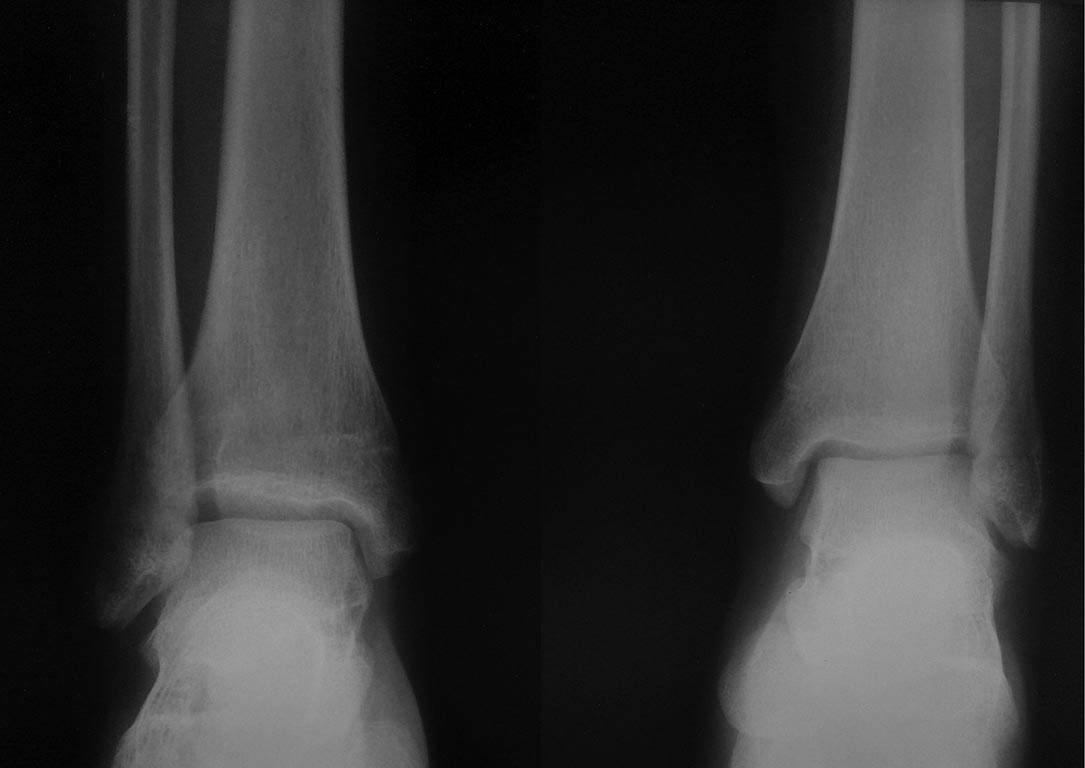

[Ortho] Последствия травмы у подростка

Снимки

Имя     : lat.jpg